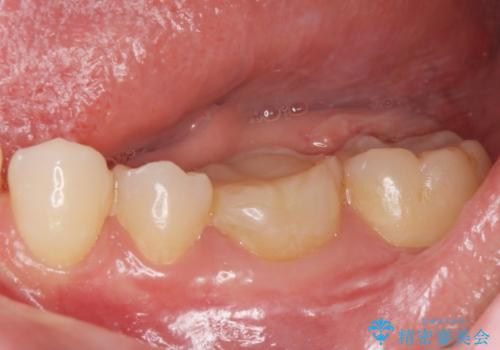

白い被せ物を入れたい。

- 他院で根管治療を終えて被せ物を入れたいとの事で来院。

形を整えて型取りをし、ジルコニアクラウンを装着しました。

被せ物が入りました。

根管治療が終わった歯は被せ物を装着しないと細菌が根管内に侵入し根の再発のリスクが増えるため早急に被せ物を入れる事をお勧めします。